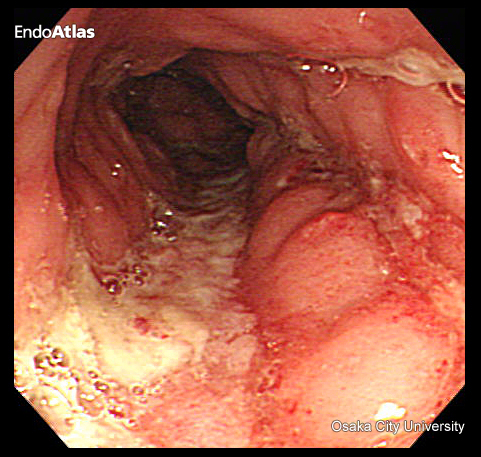

大腸がん

大腸がんは悪性疾患で、進行すると命に関わる病気です。

初期の大腸がんは、症状は特に出ませんが、進行すると、

- 血便や下血

特に肛門近くのがんでは、痔と見分けがつきにくい赤い血が出ることもあります。

また、痔と大腸がんが同時に存在している場合もあり要注意です。

大腸がんは大腸内視鏡検査で早期発見することができます。

「赤い血だから痔からの出血だろう」と自己判断して放置せずに、出血がある場合は必ず医療機関を受診してください。